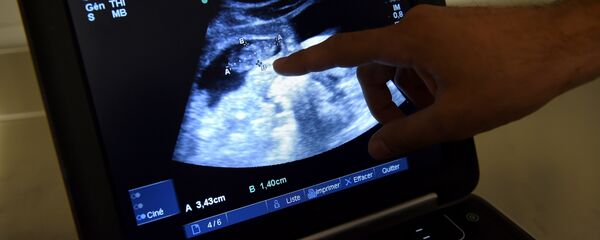

Doktor Liu, 67 yaşındaki anne Tian'ın yumurtalıklarının, 40'lı yaşlardaki kadınların yumurtalıklarıyla benzer durumda olduğunu söyledi.

Bebeğin, 2.56 kilogram doğduğu bilgisi paylaşıldı.